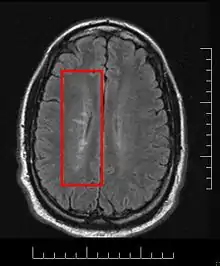

Dawson's Fingers appearing on an MRI scan

This morphologic appearance was named Dawson's fingers by Charles Lumsden, after the Scottish pathologist James Walker Dawson,[31] who first defined the condition in 1916.

Dawson's fingers

"Dawson's fingers" is the name for the lesions around the ventricle-based brain veins[32][33] of patients with multiple sclerosis and antiMOG associated encephalomyelitis[34]

Though once thought to be specific of MS, it is known not to be the case.[35]

The condition is thought to be the result of inflammation or mechanical damage by blood pressure[30] around long axis of medular veins.

Dawson's fingers spread along, and from, large periventricular collecting veins, and are attributed to perivenular inflammation.[36]

Lesions far away from these veins are known as Steiner's splashes.[30]